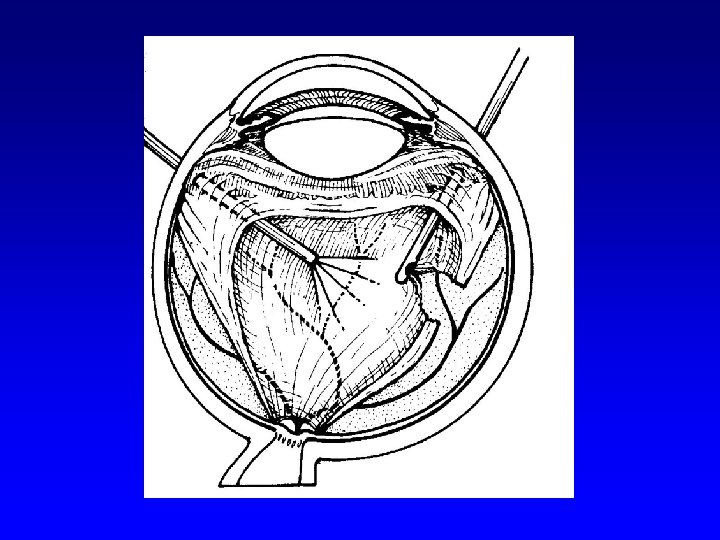

Surgical therapy of DR • Pars plana vitrectomy- (Machemer, Parel – 1970)